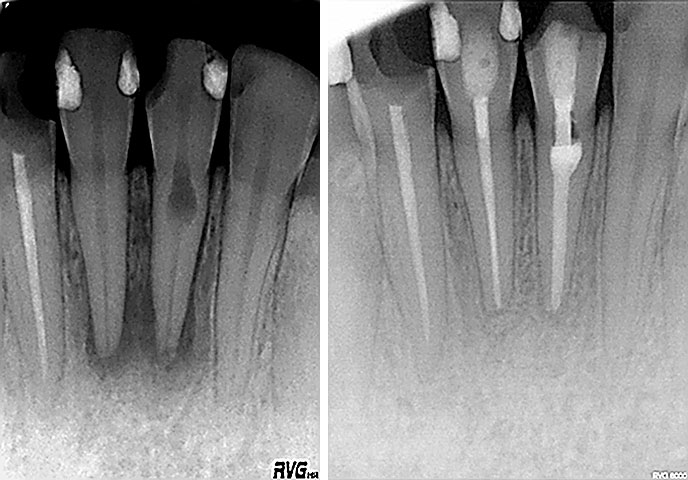

Implantologija